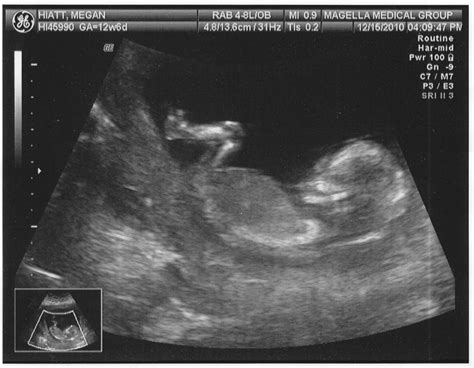

Pregnancy is an exciting journey filled with milestones, and one of the most anticipated moments is the 13 week ultrasound. This scan, typically performed between 12 and 13 weeks of gestation, offers a wealth of information about the developing fetus and the mother's health. Understanding what to expect during this ultrasound can help alleviate anxiety and prepare expectant parents for this crucial check-up.

A 13 week ultrasound is a routine prenatal test that uses high-frequency sound waves to create images of the fetus and the uterus. This scan is usually performed transabdominally, meaning the ultrasound probe is moved over the mother's abdomen. In some cases, a transvaginal ultrasound may be used for a clearer view, especially if the fetus is positioned in a way that makes it difficult to see through the abdomen.

During the 13 week ultrasound, the expectant mother will lie on an examination table with her abdomen exposed. A gel is applied to the abdomen to enhance the transmission of sound waves. The ultrasound technician will then move the probe over the abdomen to capture images of the fetus and uterus.

The procedure is painless and typically takes about 20-30 minutes. The technician will measure the fetus's CRL and assess various structures, including the heart, brain, spine, and limbs. The nuchal translucency measurement, which involves measuring the fluid behind the fetus's neck, is also performed during this scan.

Key Findings from the 13 Week Ultrasound

The 13 week ultrasound provides valuable information about the fetus's development. Some of the key findings include:

• Crown-to-Rump Length (CRL): This measurement helps confirm the due date and assess the fetus's growth.

• Nuchal Translucency (NT): This measurement helps screen for chromosomal abnormalities. A thicker NT measurement may indicate an increased risk of conditions like Down syndrome.

• Fetal Heartbeat: The heartbeat is usually visible and can be heard using a Doppler device. A normal heart rate at this stage is between 120 and 160 beats per minute.

• Fetal Anatomy: The ultrasound can reveal the fetus's head, body, limbs, and internal organs. Any abnormalities in these structures can be detected and further evaluated.

• Placenta and Amniotic Fluid: The position of the placenta and the amount of amniotic fluid are assessed to ensure the fetus is developing in a healthy environment.